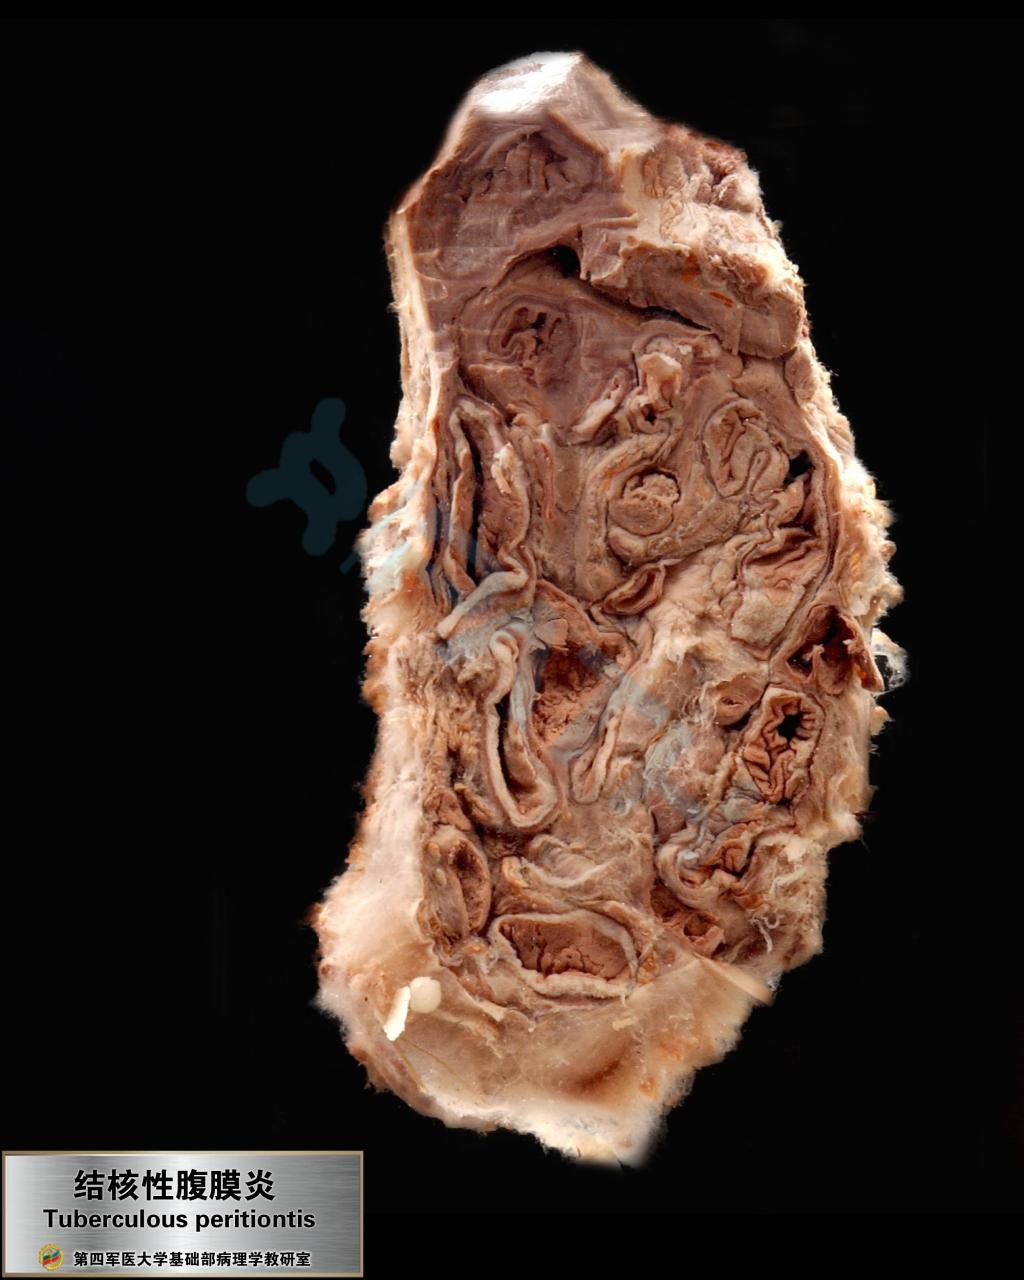

结核性腹膜炎